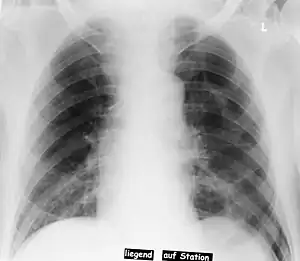

Deep sulcus sign

In radiology, the deep sulcus sign on a supine chest radiograph is an indirect indicator of a pneumothorax.[1][2] In a supine film, it appears as a deep, lucent, ipsilateral costophrenic angle[3] within the nondependent portions of the pleural space as opposed to the apex (of the lung) when the patient is upright. The costophrenic angle is abnormally deepened when the pleural air collects laterally, producing the deep sulcus sign.[4]

| Pneumothorax left sided | |

| Differential diagnosis | pneumothorax |